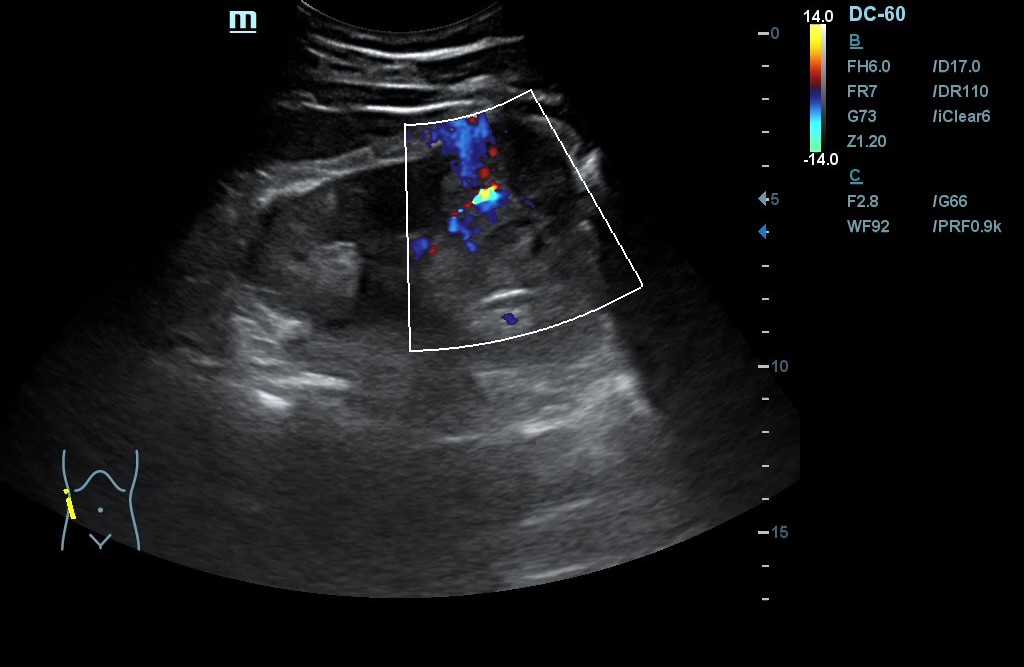

- POCUS: Lesión en polo inferior de riñón derecho (RD) de 6,2 x 5,02 cm de diámetro, con neovascularización y zonas hiperecogénicas. No signos de hidronefrosis. Disminución del flujo venoso con Doppler pulsado. Resultados compatibles con masa renal sólida a filiar. RI sin alteraciones. Jets vesicales presentes. Próstata de contornos regulares y ecogenicidad homogénea. Volumen prostático de 44 cm3.